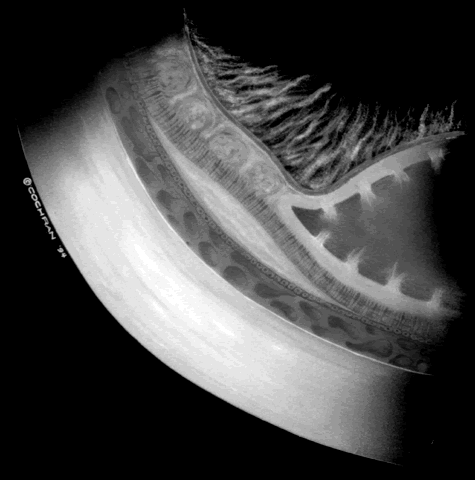

Fig. 4. A predominantly effusive stage 4B retinal detachment.

Fig. 5. A predominantly tractional stage 4B retinal detachment.